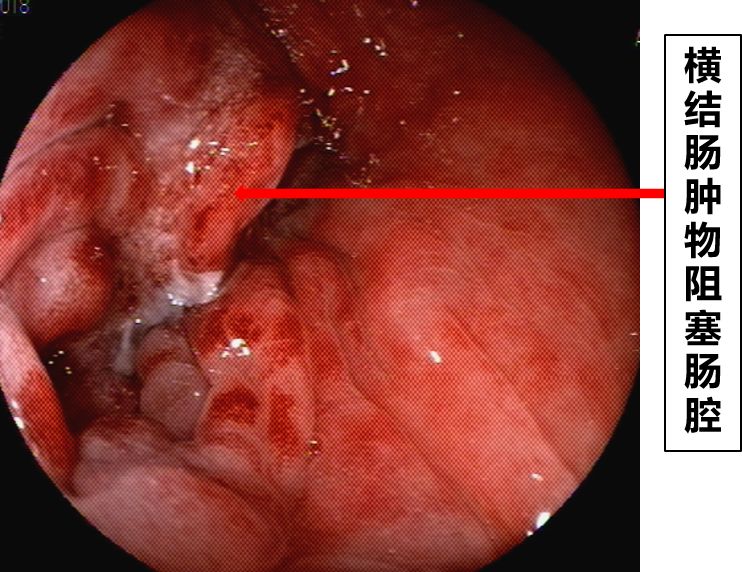

到此为止,患者已经接受了3次大的腹部手术,并接受了放化疗。但是,疾病仍然进展。2018年6月下旬患者出现恶心、呕吐,腹痛、腹胀,不能进食,X线腹部平片及腹部CT检查提示肠梗阻合并感染(见图1、图2),给予抗炎对症治疗效果差。结肠镜检查见横结肠占位伴梗阻(图3)。患者腹痛腹胀进行性加重,出现高热、血压下降等感染性休克症状。患者已经无法耐受再次开腹手术!

图3 结肠镜检查发现横结肠占位伴梗阻